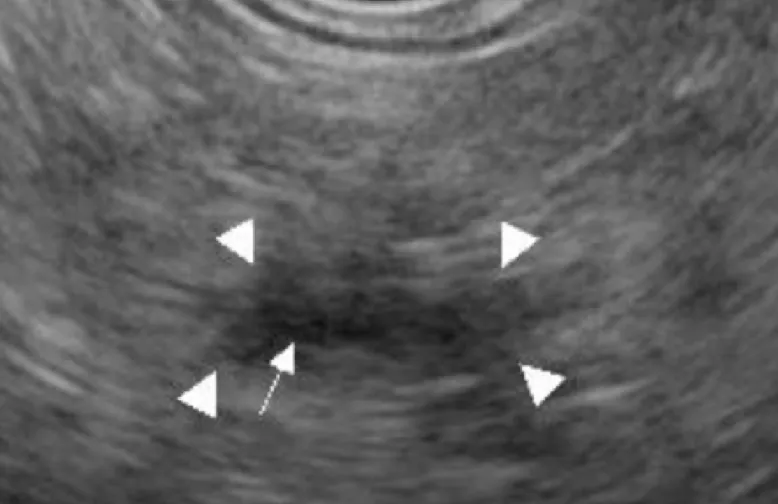

胆膵部門の特徴の1つとして膵がん早期発見の試みがあります。膵がんは固形がんの中で予後最悪と言われていますが、直径10mmまでのサイズで発見できた場合には5年生存率(5年生きられる確率)が90%以上と最新のデータで発表されています。これらを見つけることは通常の画像診断では難しく、早期膵がんに特殊な所見を発見する必要があります。特殊な所見とは小さながんが存在することによって起きてくる間接的な画像所見を指し、・主膵管拡張/狭窄・分枝膵管拡張・膵実質限局性萎縮・膵管周囲低エコー等があります(画像はSagami R et al. Cancers 2021より引用)。

これらは全てStage 0の膵がんの方の画像所見であり、通常のCTやMRIでも確認できる他、EUSを用いてより詳細に発見することもできます。これまでに多数の早期膵がんを診断・治療した実績は世界的にも認められており、大分の患者さまにも良質な診断・治療を受けて頂くことが出来ます。

• 主膵管・分枝膵管拡張

• 膵実質限局性萎縮

• 膵管周囲低エコー